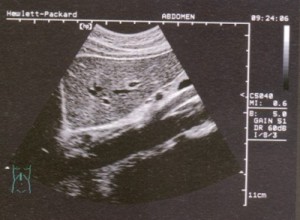

(三)B型超聲檢查

此法不僅能發現腹腔內積血,而且對肝包膜下血腫和肝內血腫的診斷也有幫助,臨床上較常用。